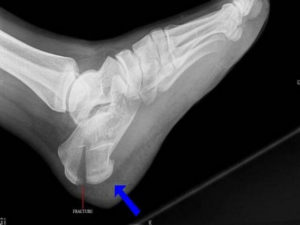

Определить перелом пяточной кости по снимку не всегда возможно. Пяточная кость – это крепкая массивная структура. При неполном переломе линия просветления четко не прослеживается.

Нет существенного смещения отломков, которое позволило бы достоверно установить диагноз. При расхождении между рентгенологическими данными и объективным состоянием травматологи назначают дополнительное обследование – компьютерную томографию.

Поперечные срезы помогают визуализировать структуру кости, четко выявлять даже мелкие трещины.

С помощью рентгена в первую очередь оценивается целостность пяточной кости. Затем анализируют её форму и расположение по отношению к другим костям стопы. При выявлении переломов пятки изучается их локализация и направленность. Если перелом оскольчатый, важно оценить, как расположены осколки, нет ли смещения.